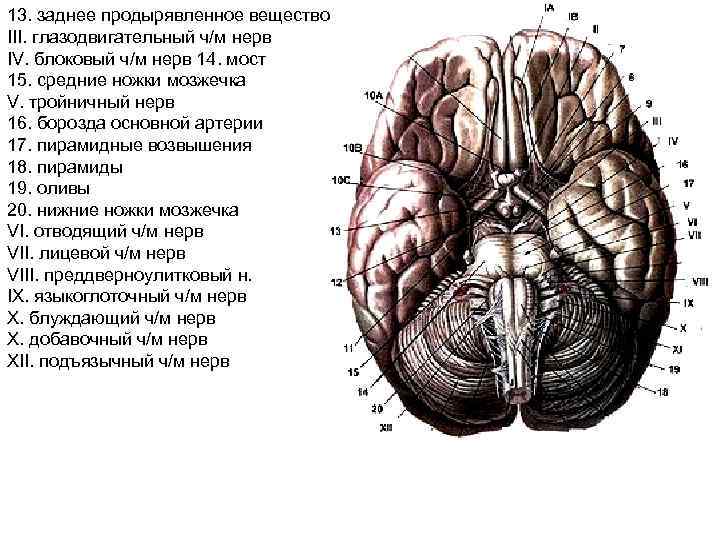

13. заднее продырявленное вещество III. глазодвигательный ч/м нерв IV. блоковый ч/м нерв 14. мост 15. средние ножки мозжечка V. тройничный нерв 16. борозда основной артерии 17. пирамидные возвышения 18. пирамиды 19. оливы 20. нижние ножки мозжечка VI. отводящий ч/м нерв VII. лицевой ч/м нерв VIII. преддверноулитковый н. IX. языкоглоточный ч/м нерв X. блуждающий ч/м нерв X. добавочный ч/м нерв XII. подъязычный ч/м нерв

13. заднее продырявленное вещество III. глазодвигательный ч/м нерв IV. блоковый ч/м нерв 14. мост 15. средние ножки мозжечка V. тройничный нерв 16. борозда основной артерии 17. пирамидные возвышения 18. пирамиды 19. оливы 20. нижние ножки мозжечка VI. отводящий ч/м нерв VII. лицевой ч/м нерв VIII. преддверноулитковый н. IX. языкоглоточный ч/м нерв X. блуждающий ч/м нерв X. добавочный ч/м нерв XII. подъязычный ч/м нерв